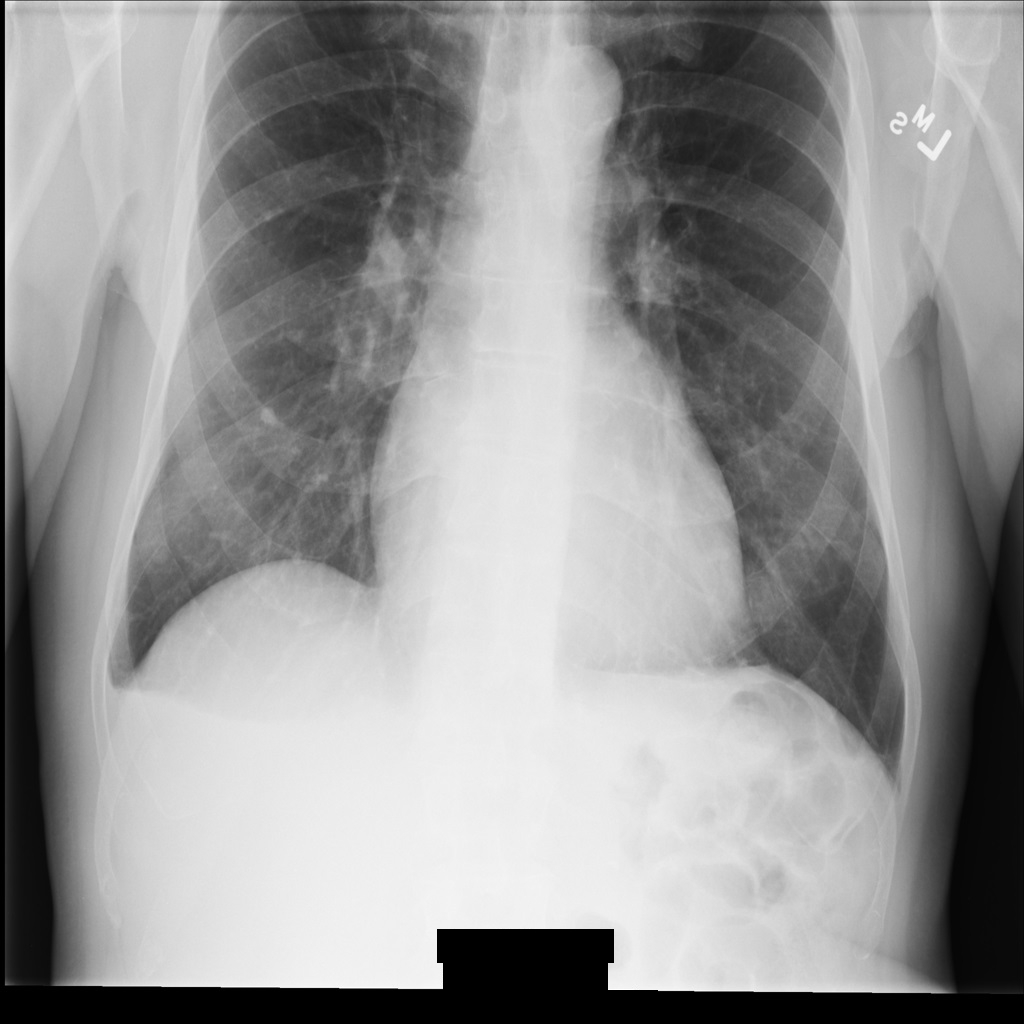

サンプル画像

このページの一部のサンプルには、匿名化された画像の出力が含まれています。各例では、入力として以下の元画像を使用しています。各匿名化オペレーションからの出力イメージをこの元のイメージと比較して、オペレーションの効果を確認できます。

REDACT_ALL_TEXT を使用して画像を匿名化すると、画像は次のようになります。画像の下部にある焼き付きテキストがすべて秘匿化されていることに注目してください。

REDACT_ALL_TEXT を使用して匿名化された後の DICOM インスタンス。Clean Descriptors オプションを使用して機密テキストを秘匿化する

REDACT_SENSITIVE_TEXT_CLEAN_DESCRIPTORS を使用して画像を匿名化すると、画像は次のようになります。画像の下部にある焼き付きテキストの一部が秘匿化されていないことに注意してください。PatientSex (0010,0040) はデフォルトの DICOM infoType の 1 つではないため、テキスト Female は引き続き表示されます。

REDACT_SENSITIVE_TEXT_CLEAN_DESCRIPTORS を使用して匿名化された後の DICOM インスタンス。DICOM タグを匿名化する